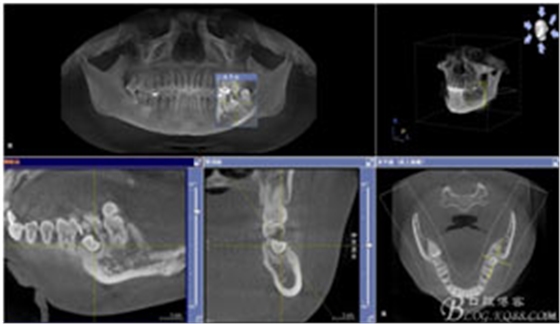

患者、申xx、女、40歲,主訴:左側(cè)下頜后牙牙齦紅腫不適數(shù)月。專科檢查:37合面有一開髓孔。髓腔內(nèi)有一暫封小棉球,探針?biāo)枨坏撞砍鲅?,疑為在外院治療?dǎo)致底穿。x線片檢查:37頰側(cè)齦下有一枚多生牙,多生牙壓迫頰側(cè)牙根及牙體組織大量吸收。

圖1.術(shù)前的CBCT檢查:37頰側(cè)部分牙根被完全壓迫吸收。